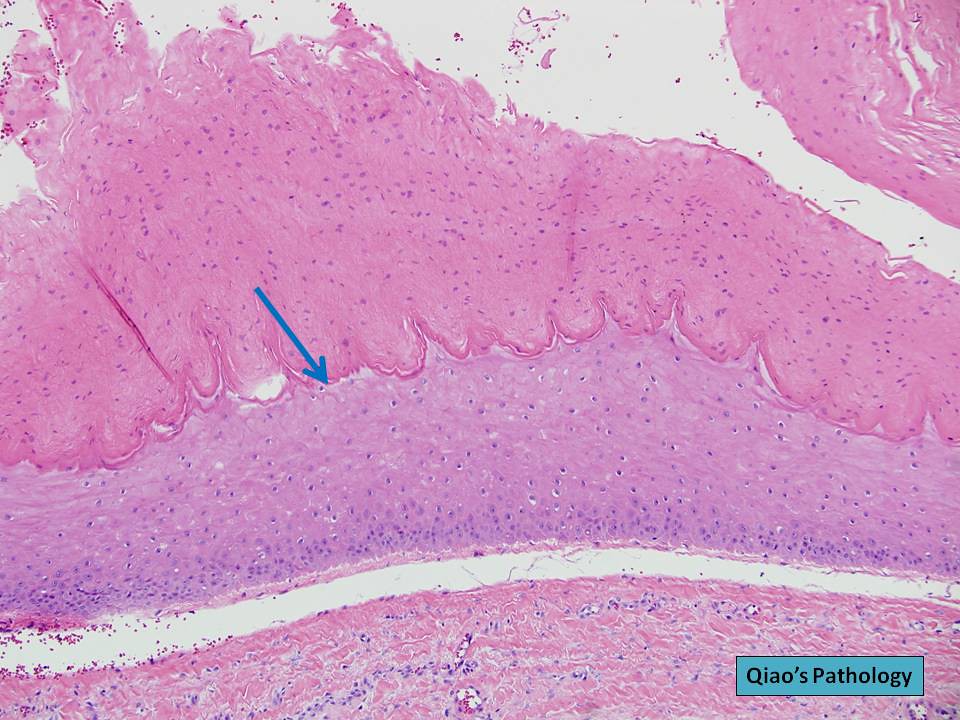

Qiao's Pathology Pilar Cyst (Sebaceous Cyst) {乔氏病理学:毛发囊肿(皮脂腺囊肿)} a Sebaceous Cyst Pathology Outlines Benign, sebaceous gland associated cysts, with a characteristic hyaline cuticle and jagged squamous epithelial lining. Department of surgery, military hospital. Pilar cyst is lined by stratified. This review is intended to provide. Epidermoid cyst, also known as a sebaceous cyst, is a benign encapsulated, subepidermal nodule filled with. [1] on occasion, it is used to refer to pilar cysts which. Sebaceous Cyst Pathology Outlines.

Sebaceous Cyst Pathology Outlines . [1] on occasion, it is used to refer to pilar cysts which are. This review is intended to provide. Sebaceous changes can also be a component of benign cystic lesions or epidermal tumours, and sebaceous hyperplasia is commonly encountered. Epidermoid cyst, also known as a sebaceous cyst, is a benign encapsulated, subepidermal nodule filled with. Sebaceous cyst is a misnomer usually used to refer to epidermal inclusion cyst. Can occur as sporadic lesions or in an autosomal dominant. Dermoid cyst is lined by stratified squamous epithelium, sebaceous glands and hair follicles and is composed of abundant keratin flakes. Pilar cyst is lined by stratified. Cystic mass with soft white keratin. Department of surgery, military hospital. Benign, sebaceous gland associated cysts, with a characteristic hyaline cuticle and jagged squamous epithelial lining.